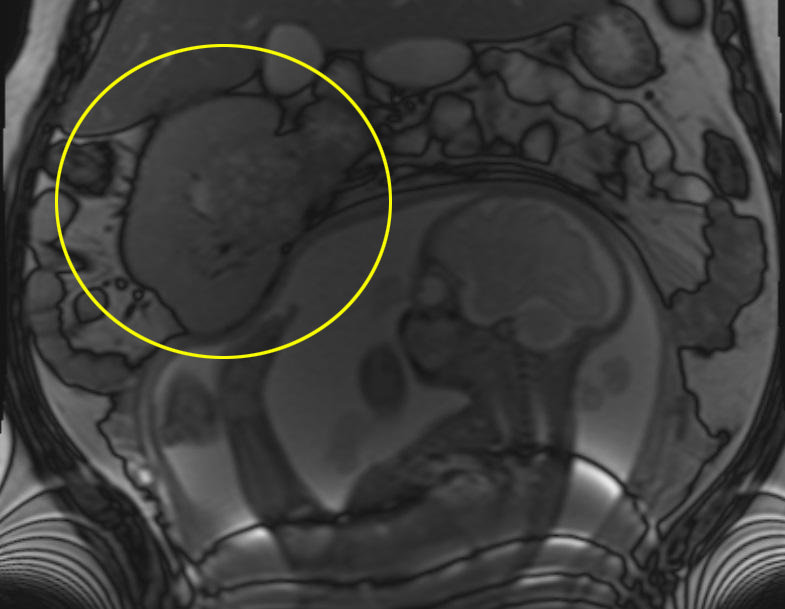

영국 그리니치에 사는 수잔 오플라나간(san O’Flanagan·40)씨는 임신 20주에 초음파 검사를 하러 병원에 갔다가 깜짝 놀랐습니다. 오른쪽 신장에 태아 머리만 한 종양이 보인 것입니다.

임신 중이라 14㎝나 되는 종양의 정체를 알 수가 없었습니다. 암인지 알아보려면 CT 촬영을 해야 하는데 이 경우 방사선이 다량 체내에 투입되기 때문에 태아에게 치명적일 수 있습니다.